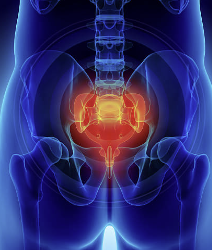

꼬리뼈는 인간의 척추뼈 구조 중 하나로, 척추 열의 맨 아래쪽에 위치합니다. 꼬리뼈은 척추의 일부이지만, 현대인들은 더 이상 꼬리를 갖고 있지 않으므로 기능을 하지 않습니다. 하지만 꼬리뼈는 인간의 진화적 역사에서 중요한 역할을 했었습니다. 리뼈는 뼈 자체로는 작지만, 다리와 척추를 연결하고 균형을 잡는 역할을 하며, 혹은 충격을 흡수하여 상해를 예방하는 역할을 합니다.

꼬리뼈 부근 통증은 다양한 원인에 의해 발생할 수 있습니다. 일반적으로 꼬리뼈 자체에 직접적인 문제가 있는 것은 드뭅니다. 대부분의 경우 꼬리뼈 주변 조직에 문제가 생긴 것이 원인입니다.

또한 균형을 잡는 역할을 하는 꼬리뼈가 상해를 입었을 경우에도 통증이 발생할 수 있습니다. 스포츠나 활동 중에 발생한 외상적인 충격이나 낙상 등으로 인해 꼬리뼈가 상해를 입으면 주변 조직에 염증이 발생하고 통증이 나타납니다.

또한 뼈 조직이 아닌 주변 조직인 인대, 근육, 신경 등에 문제가 생긴 경우에도 꼬리뼈 부근 통증이 발생할 수 있습니다. 척추 디스크의 이상으로 인해 디스크가 꼬리뼈 부근으로 압박되면 인대와 근육에 긴장이 생겨 통증을 유발합니다. 또한 꼬리뼈 부근을 관통하는 신경이 염증을 일으키거나 압박을 받으면 통증이 나타납니다.